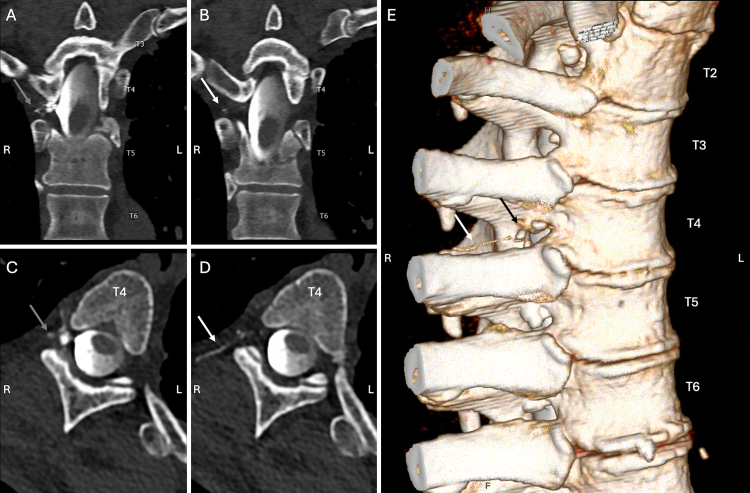

Observations: A 67-year-old male presented with severe positional headaches following minor head trauma. MRI of the brain demonstrated pachymeningeal enhancement, and dynamic CT myelography demonstrated a CVF at the right T4 nerve root. Transvenous CVF embolization was attempted, but there was no suitable target for embolization despite extensive exploration of the azygos, paraspinal, and vertebral veins above and below the fistula. The patient underwent percutaneous puncture of the right T4 paraspinal vein using an 18-gauge Chiba needle under fluoroscopic guidance. Onyx 34 was carefully injected into the CVF under continuous fluoroscopic guidance to embolize the fistula and associated paraspinal venous complex.